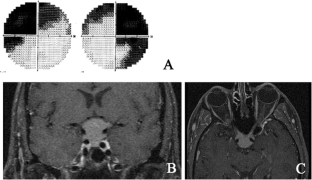

Fig. 2